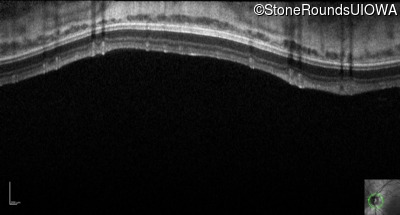

Optical Coherence Tomography - Right - 10/160 sc

Exemplar / OCT Stack

OCT Stack

Optical Coherence Tomography - Left - 10/200 sc